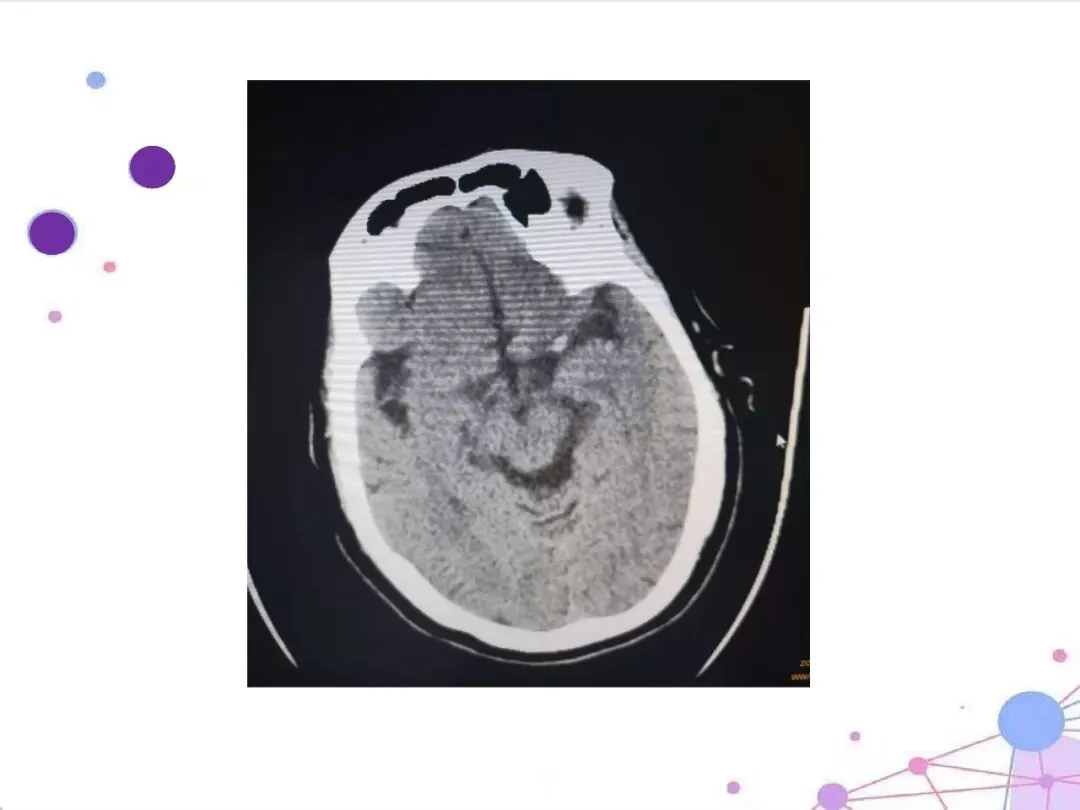

【介入PPT·可下载】大面积脑梗介入手术围术期的护理